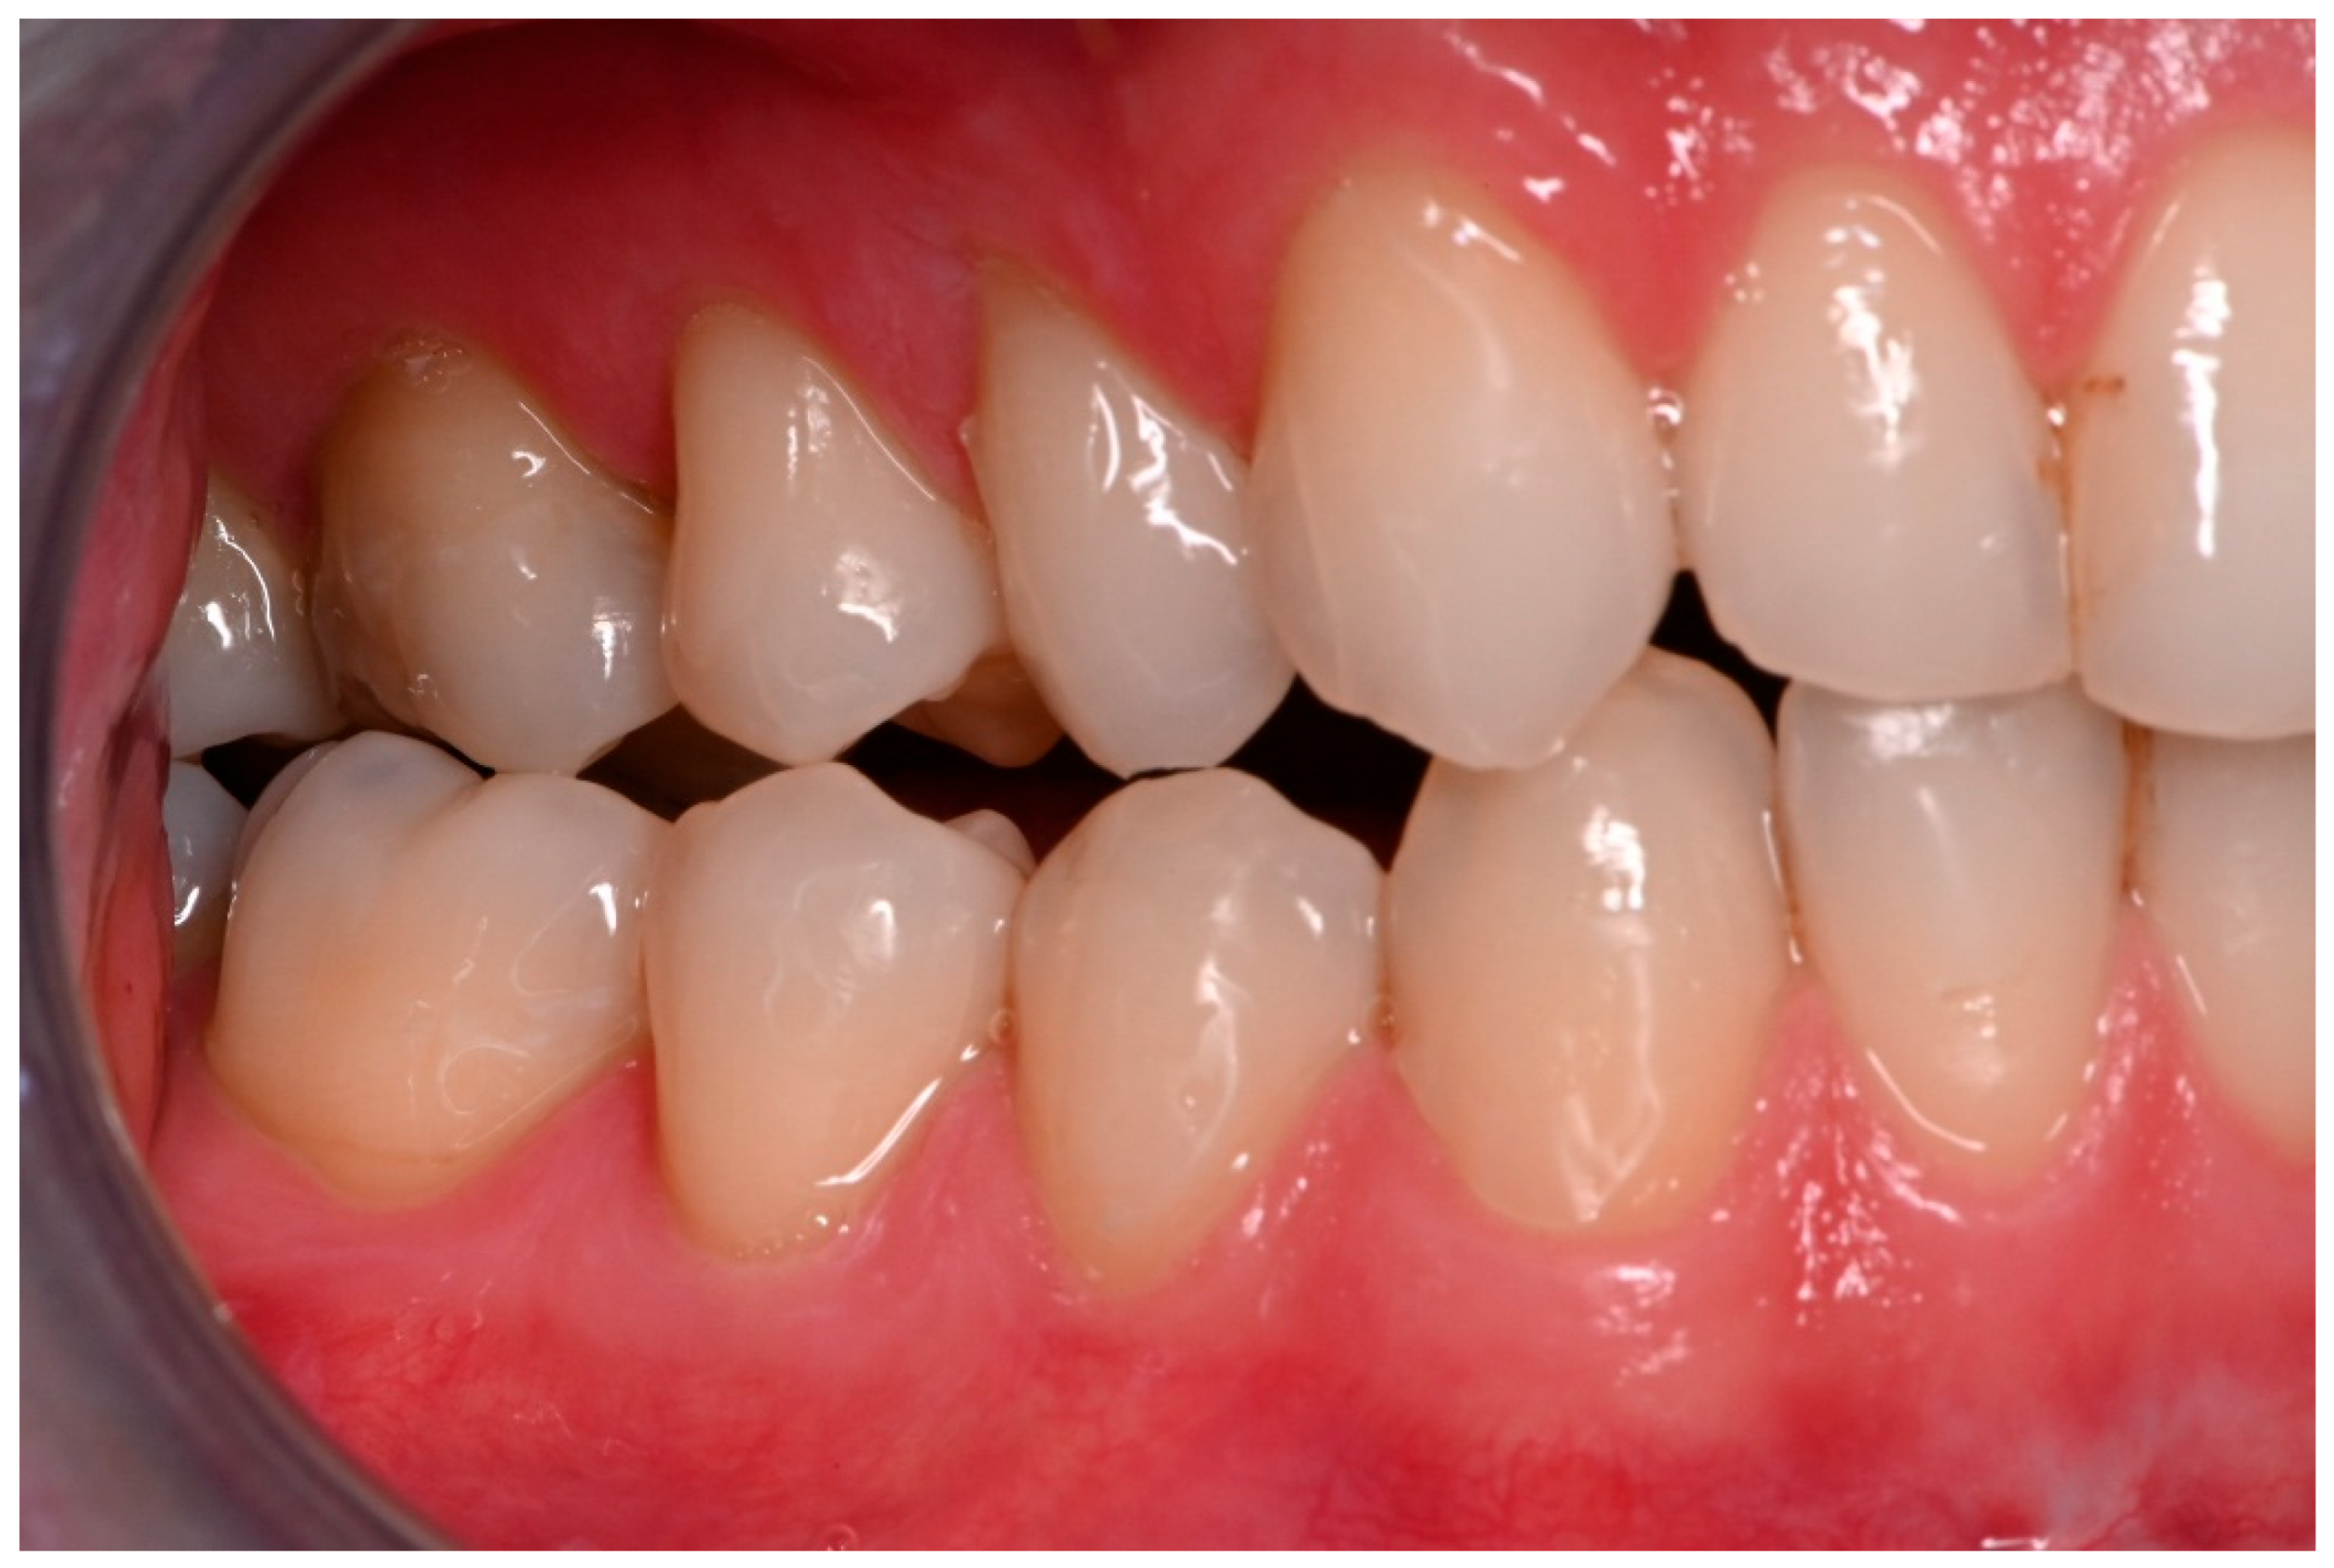

Figure 6. Inadequate occlusion with crossbite on the right-hand side after insufficient reduction in the condylar neck on the same side (see Figure 5).

Figure 7. Adequate occlusion on the left-hand side, after satisfactory reduction in the condylar neck on the same side. The lower molar crown was fractured in the accident (see Figure 5).